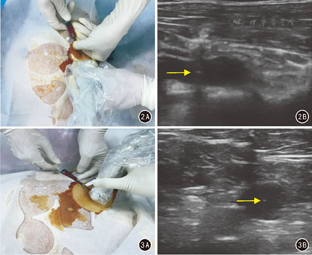

先用套有无菌保护套的B超探头观察锁骨下静脉的位置、走行及与锁骨下动脉的关系,再按传统穿刺法或改良穿刺法确定穿刺点后,在B超引导下完成锁骨下穿刺、置管、固定等操作[3]。见图2、图3。